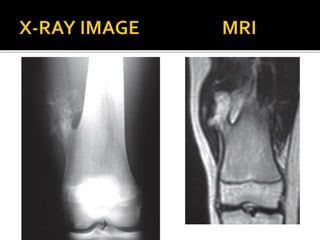

 Replacement of normal bone and marrow by

fibrous tissue and small, woven spicules of

bone. Monostotic/Polyostotic.

 Common – 1st to 3rd decades. M=F

Can occur in the epiphysis, metaphysis or

diaphysis

 Presentation – Pain, deformity, cutaneous

pigmentation and endocrine abnormalities

(McCune Albright Syndrome), sexual

precocity, intramuscular myxoma

(Mazabraud syndrome) and thyroid disease.

 Histology – Irregularly woven bone spicules

with a fibrous stroma

 Imaging – Ground glass appearance, granular

with a well-defined sclerotic rim. Small areas

of cartilaginous metaplasia and cystic

changes may be present

 Treatment – Surgical treatment – significant

deformity or pathological fracture or pain –

intramedullary fixation/osteotomy.

Treatment with bisphosphonates for

extensive disease